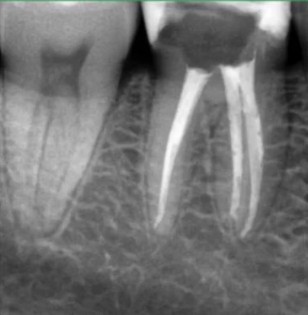

Кхалил Абаноуб Адли Абдуллах: портфолио (4)